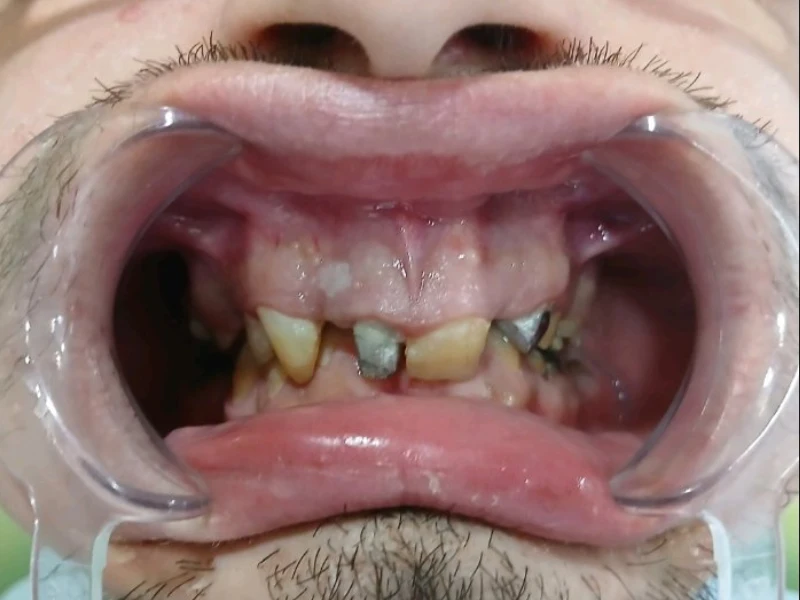

Gubitak većeg broja zuba ne utiče samo na estetiku, već i na funkciju, govor i kvalitet života.

ALL-on-X je savremeni implantološki koncept koji omogućava potpunu rehabilitaciju vilice pomoću 4, 5 ili 6 implantata (All-on-4, All-on-5, All-on-6), u zavisnosti od anatomije i kliničke procjene.

Saznajte da li ste kandidat za ALL-ON-X i koje su Vaše mogućnosti. Stručna procjena je prvi korak ka stabilnom, fiksnom i dugoročnom rješenju.